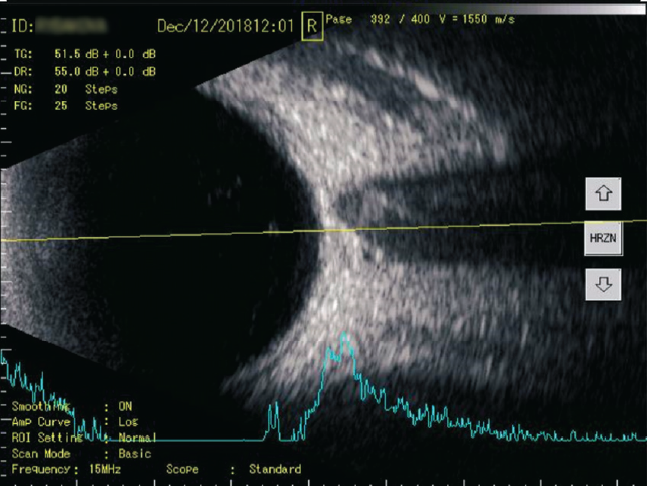

У пациентов обеих групп по окончании курса по данным комбинированного А- и В-сканирования топографические характеристики были постоянными: в 82 % случаев (р = 0,43) помутнения концентрировались в нижней половине СТ (рис. 3, 4).

Рис. 4. A- и B-сканирование пациентки П. после курса препарата «Витрокап». В-скан: поперечная проекция по меридиану 6 ч, умеренное количество помутнений в стекловидном теле. А-скан: 12 пиков низкой эхогенности

Fig. 4. After a course of the drug “Vitrocap”, patient P.: B-scan: transverse projection along the meridian to 6 hours, moderate amount of “clouding” in the vitreous body. A-scan: 12 peaks of low echogenicity

При сканировании в В-режиме после курса лечения препаратом «Витрокап» в 32 % случаев отмечено уменьшение количества помутнений, что соответствовало снижению количества эхопиков на А-сканировании (рис. 4, 6, 8), в большинстве случаев (80 %, р < 0,05) происходило снижение высоты эхопиков при А-сканировании в зоне их максимальной концентрации (см. рис. 4, 8).